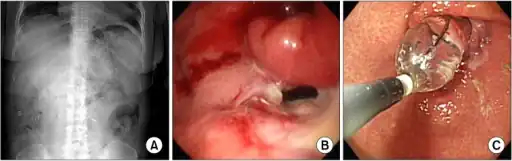

| X-ray showing a large amount of food in the stomach due to severe gastroparesis[1] | |

a-c)Radiologic and endoscopic finding of delayed gastric emptying